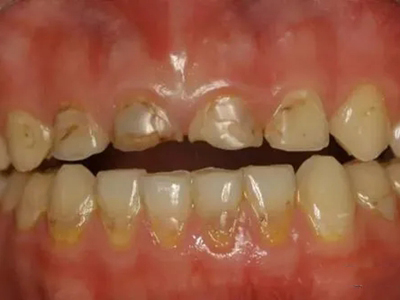

酸蚀症牙齿缺损严重有黑斑图

酸蚀症严重时会使牙齿出现大面积缺损,有三颗下牙损毁严重,露出不整齐的牙骨质边缘,几乎仅余留牙根。缺损处有黑斑,局部呈黄褐色,需积极就医进行牙齿修复。